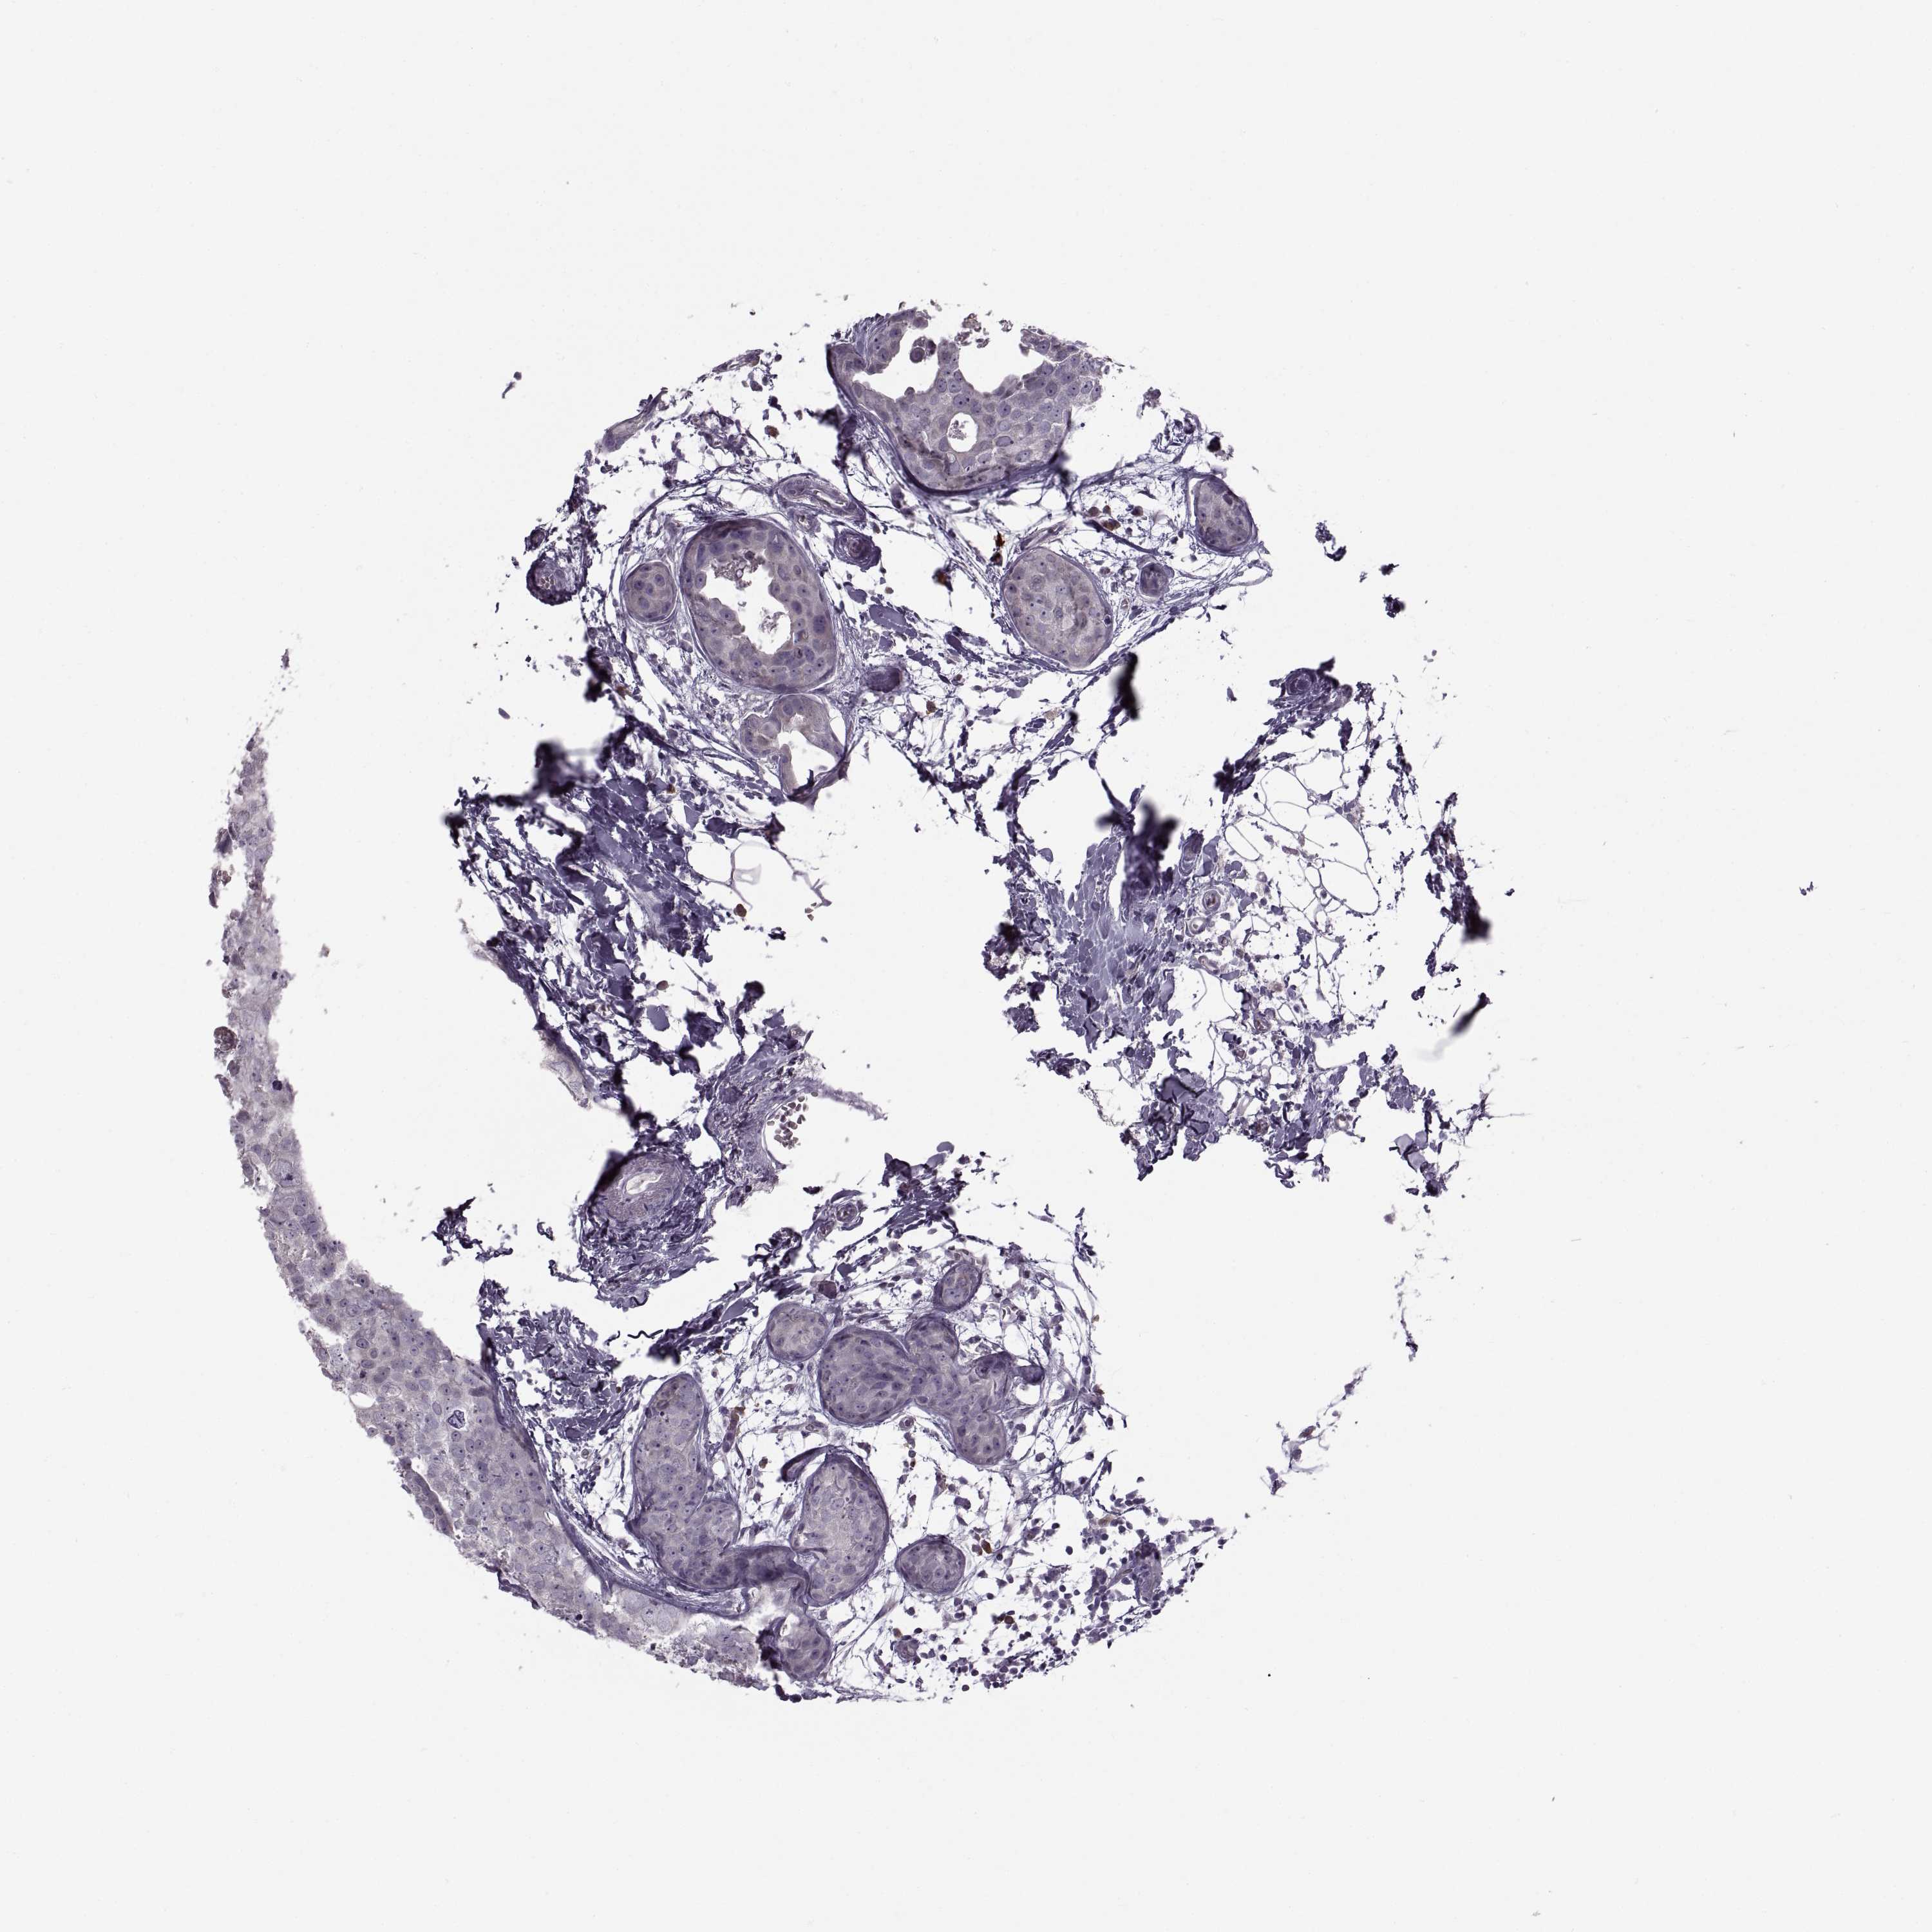

CANCER BREAST CANCER Show tissue menu

BRCA TCGA BRCA VALIDATION PROTEIN EXPRESSION